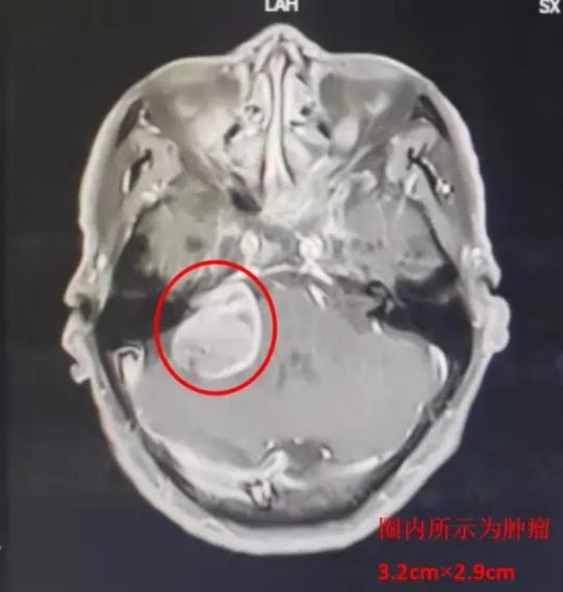

患者马某,69岁,因耳鸣及头晕2年,严重影响日常生活,3月19日就诊于乐鱼在线登录入口神经外科一病区。入院诊断:右侧听神经瘤。